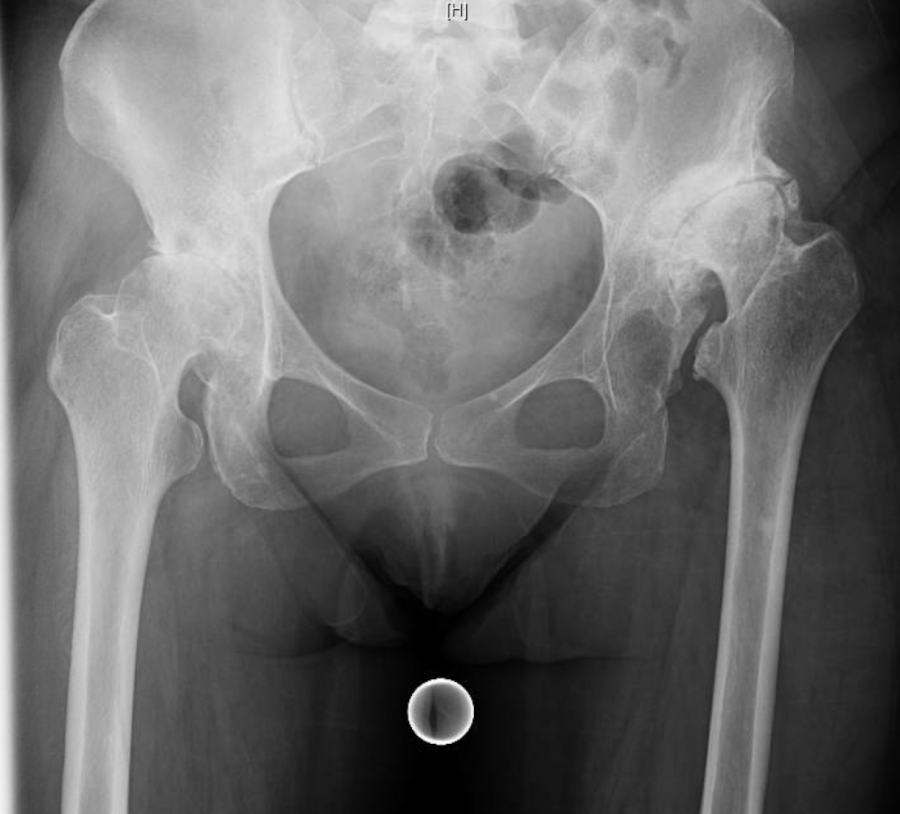

Displasia dell’anca

- Descrizione: Conosciuta come lussazione congenita dell'Anca o displasia congenita dell'anca, è uno sviluppo anormale dell'Articolazione coxo-femorale. Questo sviluppo porta la testa del femore a dislocarsi dalla cavità acetabolare. Inizia in epoca fetale e procede in età giovanile a creare problemi di stabilità ed efficienza dell'anca.